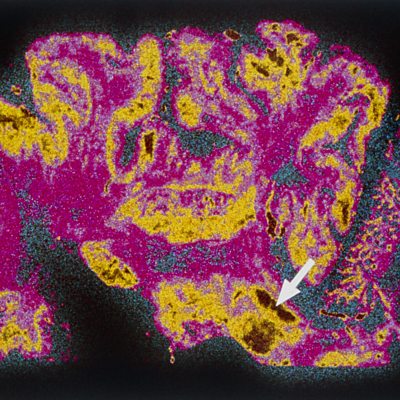

'When you are first diagnosed it is a bit of an axe falling. You are very conscious of telling people. I told very close family and friends and a couple of work colleagues. In social situations I will hide it.' David Plummer, who is a 48 year old sufferer of Parkinson’s disease joins Jeremy and the ÃÛÑ¿´«Ã½'s resident doctor, Sarah Jarvis to discuss the stigma surrounding Parkinson's. Of the 127,000 people in the UK with Parkinson's, 40% feel the need to keep it a secret. David Plummer was 40 when he was diagnosed with Parkinson's and he now helps sufferers come to terms with the disease. It has not stopped his work as a wildlife photographer. David thinks he had the disease 7 years prior to official diagnosis. A trigger point for him was a twitching arm and tremor under nervous conditions. It took 6 month to get a full diagnosis. Dr Sarah Jarvis discusses diagnosing Parkinson's through a combination of testing for tremor, poverty of movement, and rigidity. It is not just old people who get the disease.